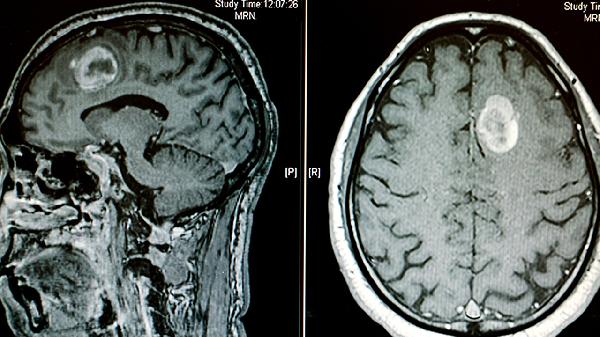

脑瘤手术费用与治疗次数有关

医院不同,病情不同,价格无法确定。脑瘤手术的费用与治疗次数和配置的药物有关,很难具体说明多少钱。根据最终剂量,成本约为500元,也需要结合当地收费标准,放疗约30次,但可以报销,他们可能负担不起太多,